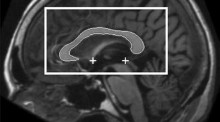

Variations in midcingulate morphology are related to ERP indices of cognitive control Rene J. HusterS. Enriquez-GeppertM. Bruchmann Original Article 22 November 2012 Pages: 49 - 60